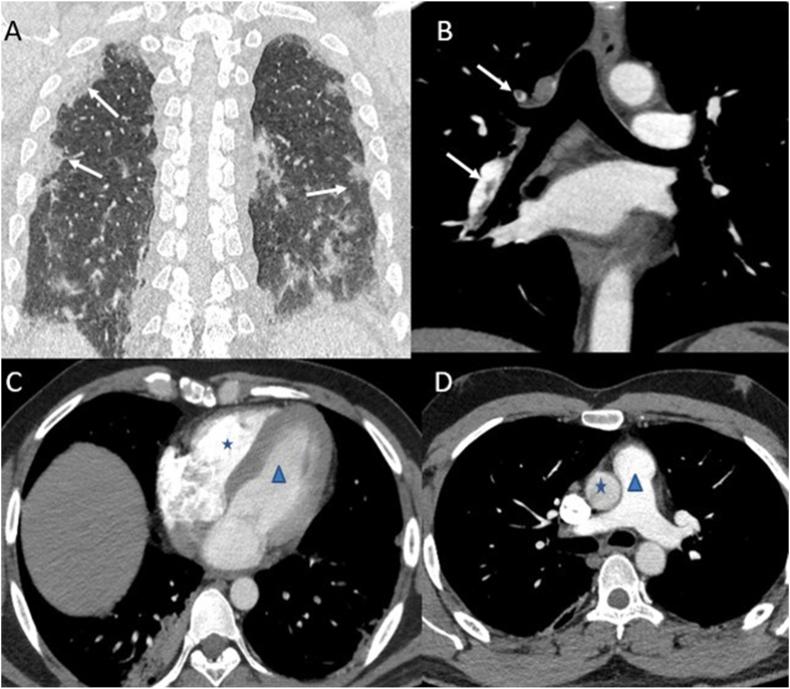

Pulmonary embolism (PE) has been identified as one of the deadliest complications of coronavirus disease 2019 (COVID-19), especially in patients admitted to the intensive care unit (ICU). Western literature reminds us of the high prevalence of PE in COVID. Here, we report a series of 13 cases of PE diagnosed and managed at our hospital.

Computed tomography pulmonary arteriography was used to make the diagnosis in eight patients (61.53%), and clinical findings with corroborative ultrasound and laboratory parameters were used to label PE in five patients (38.46%). Five patients were hemodynamically unstable, requiring thrombolysis with recombinant tissue plasminogen activator, and four patients (30.76%) suffered a fatal outcome.